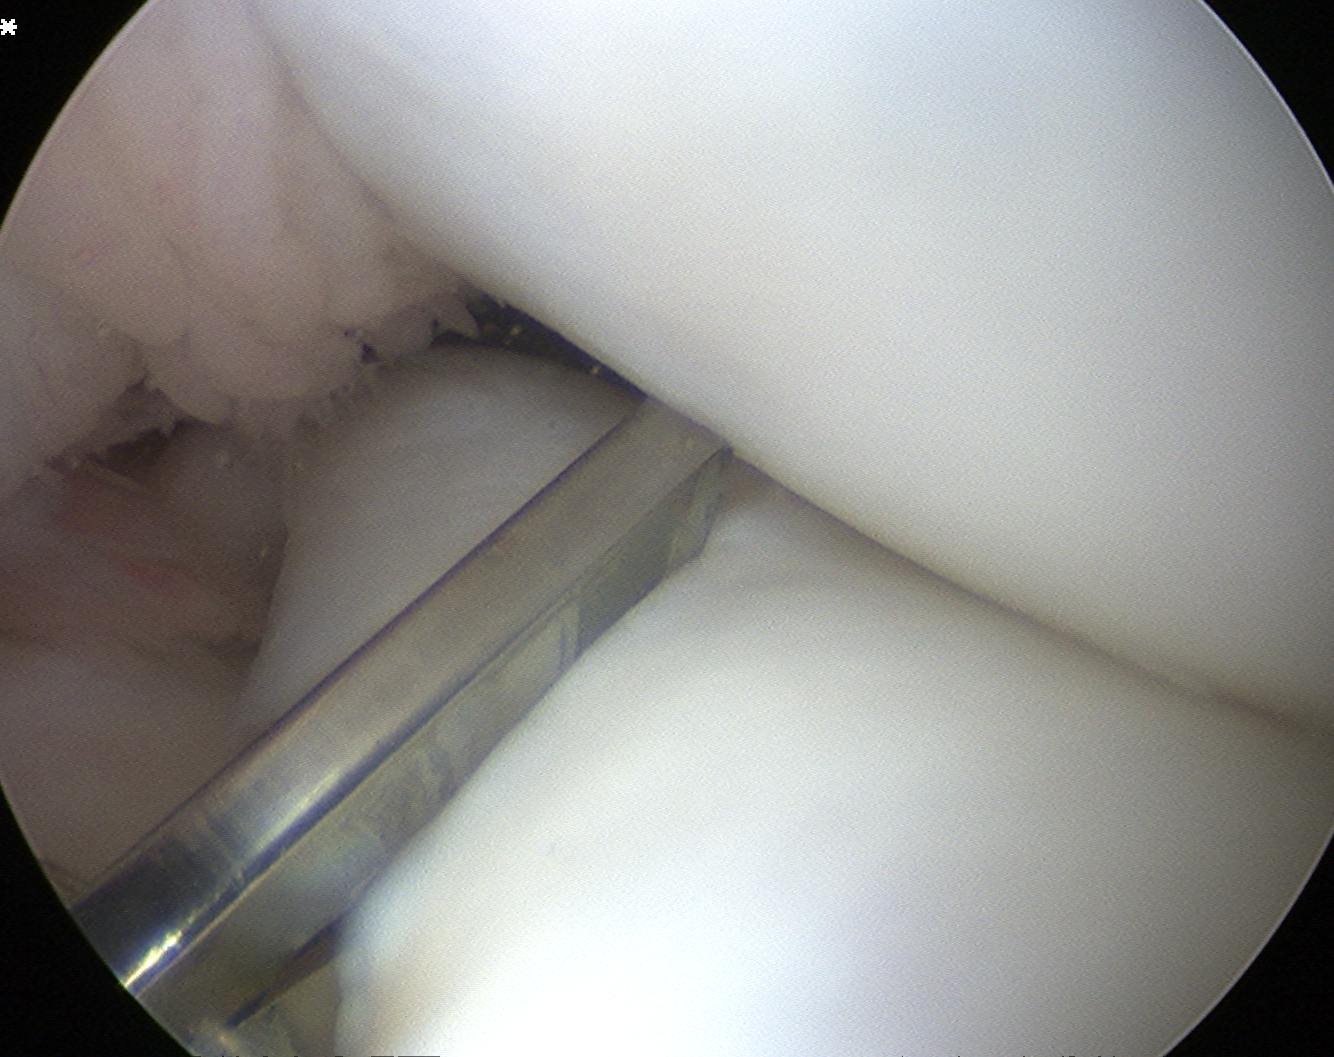

Technique Saucerisation

Issues

- demanding and technically difficult

- takes 1 - 2 hours

- difficult to know how much to resect

- need to ensure don't damage chondral surfaces

- reported cases of rapid and severe chondrolysis post resection in young patients

Technique

- make incision with scissors in medial aspect

- resect posterior part

- saucerise laterally and anteriorly

- need to ensure don't detach anterior horn